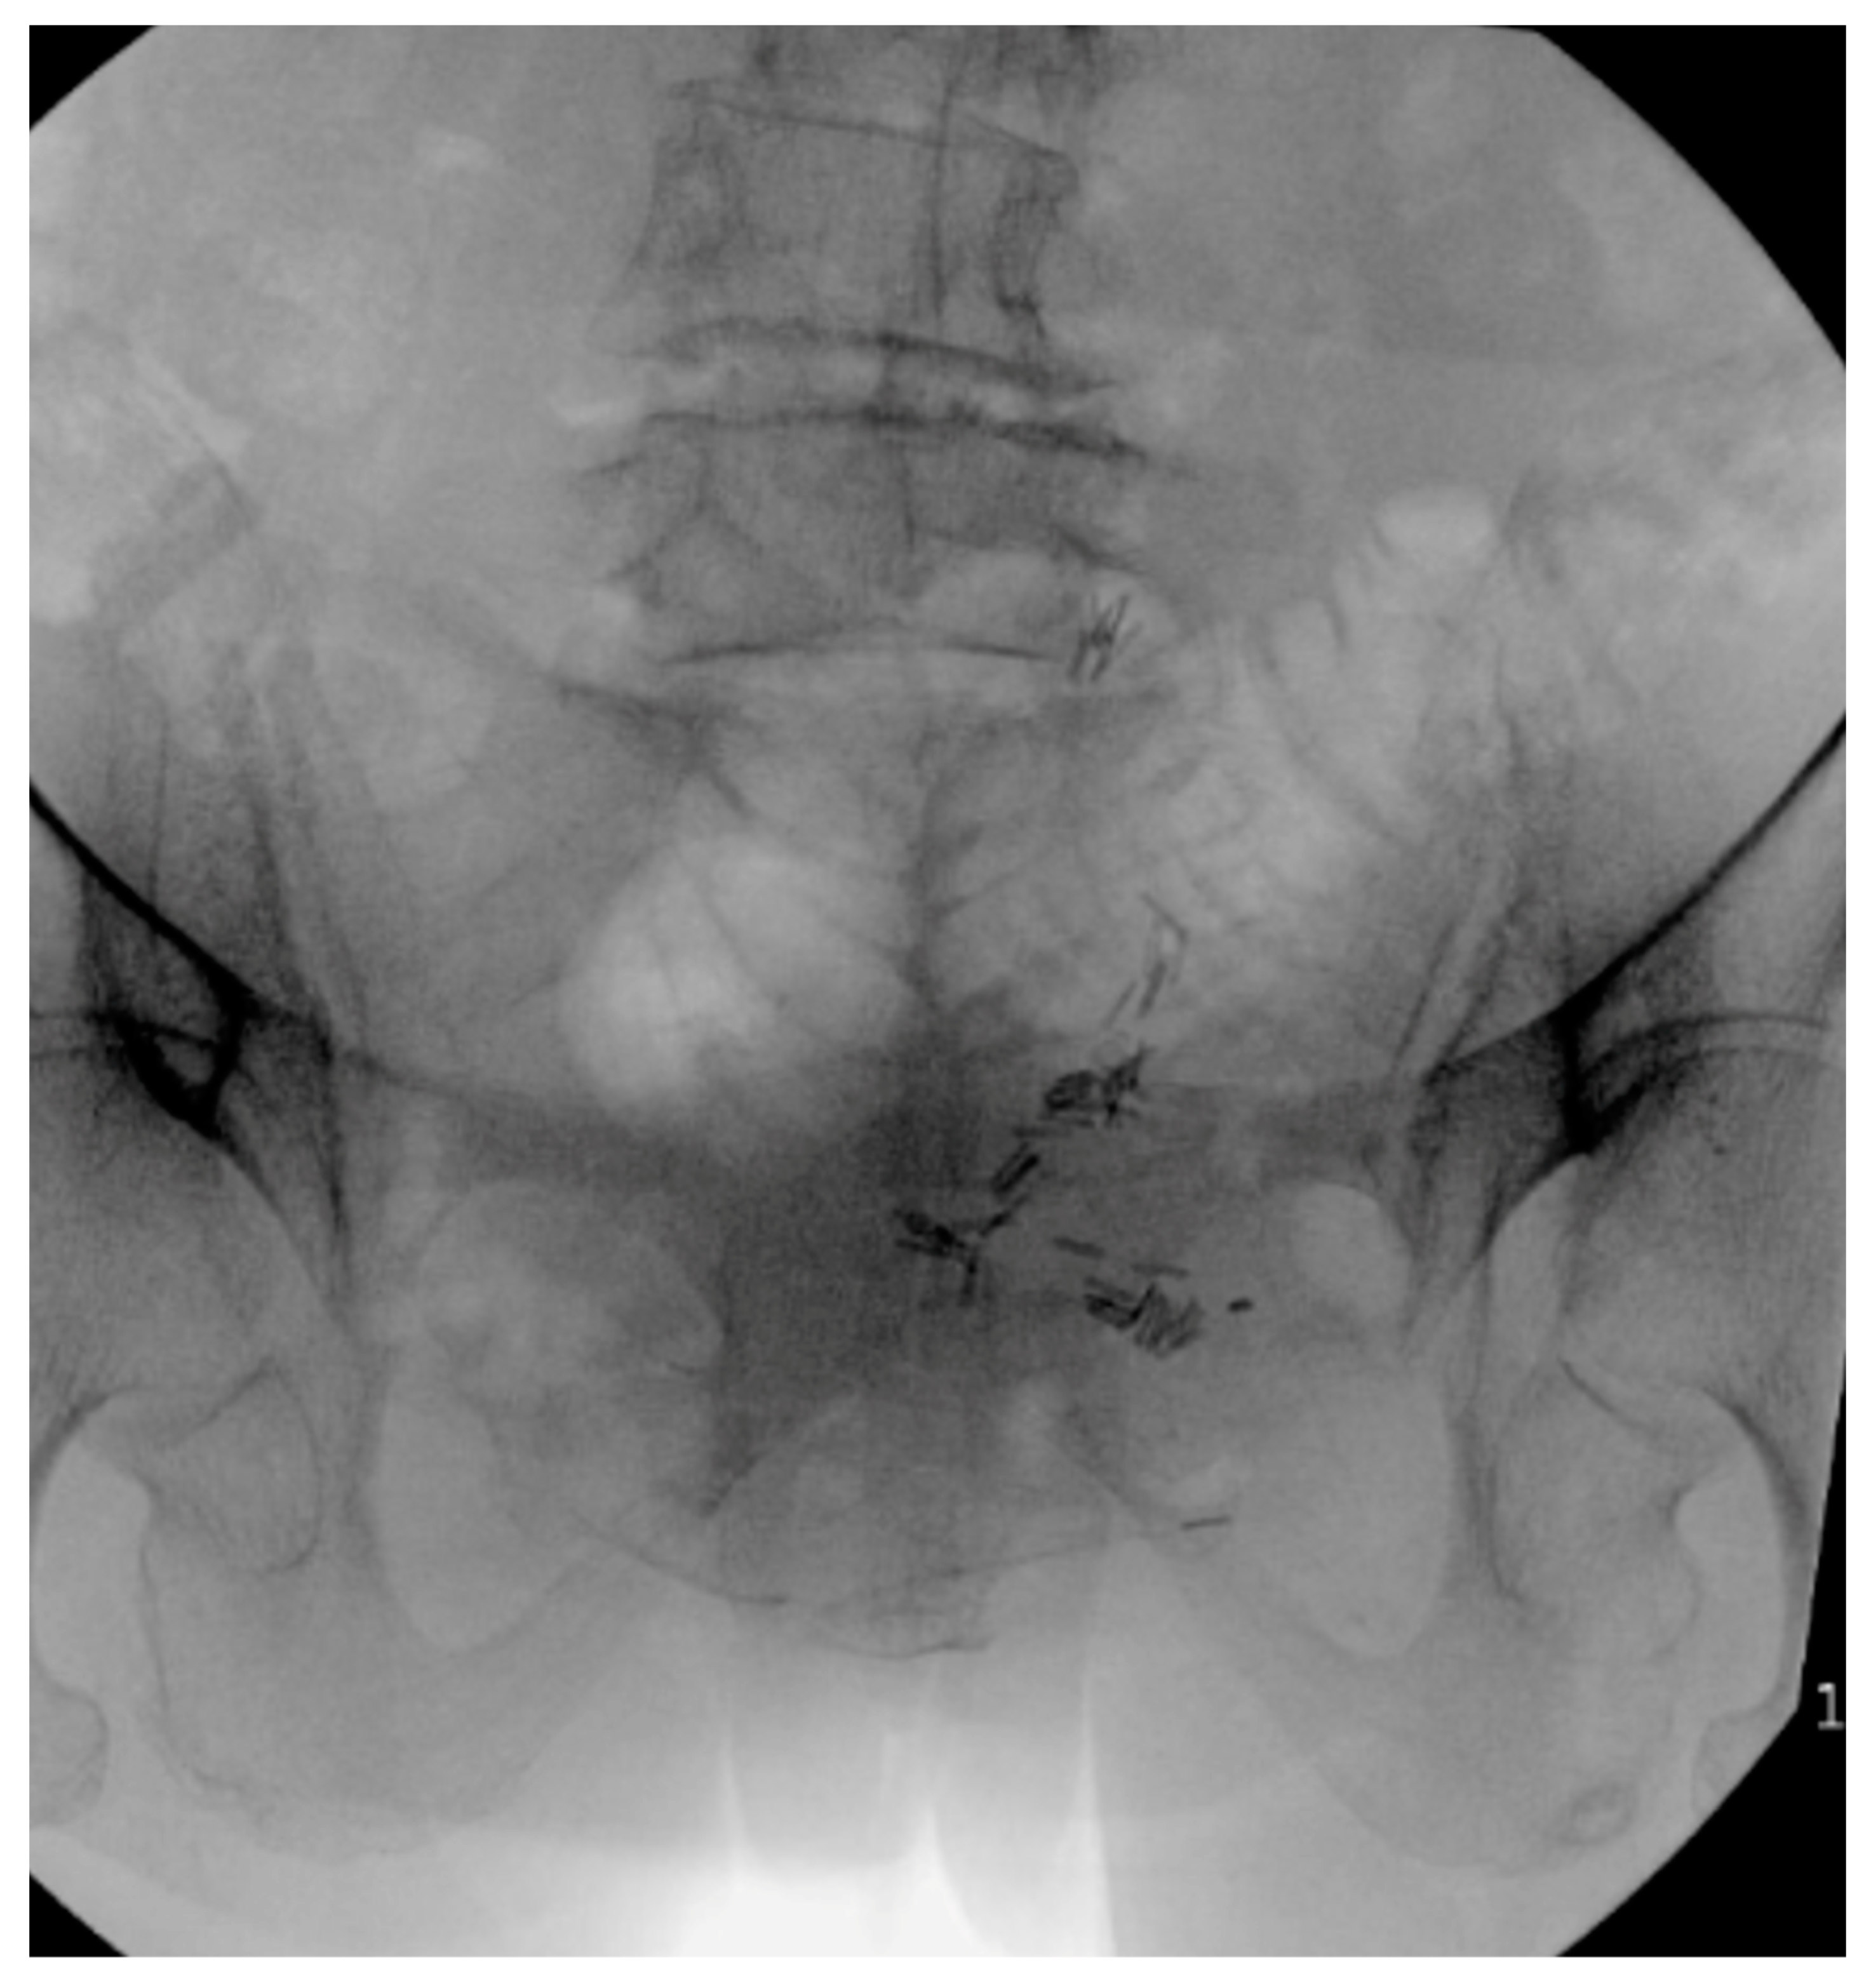

6. Spinopelvic Fixation Percutaneous Technique

7. Tran-Sacral Percutaneous Technique